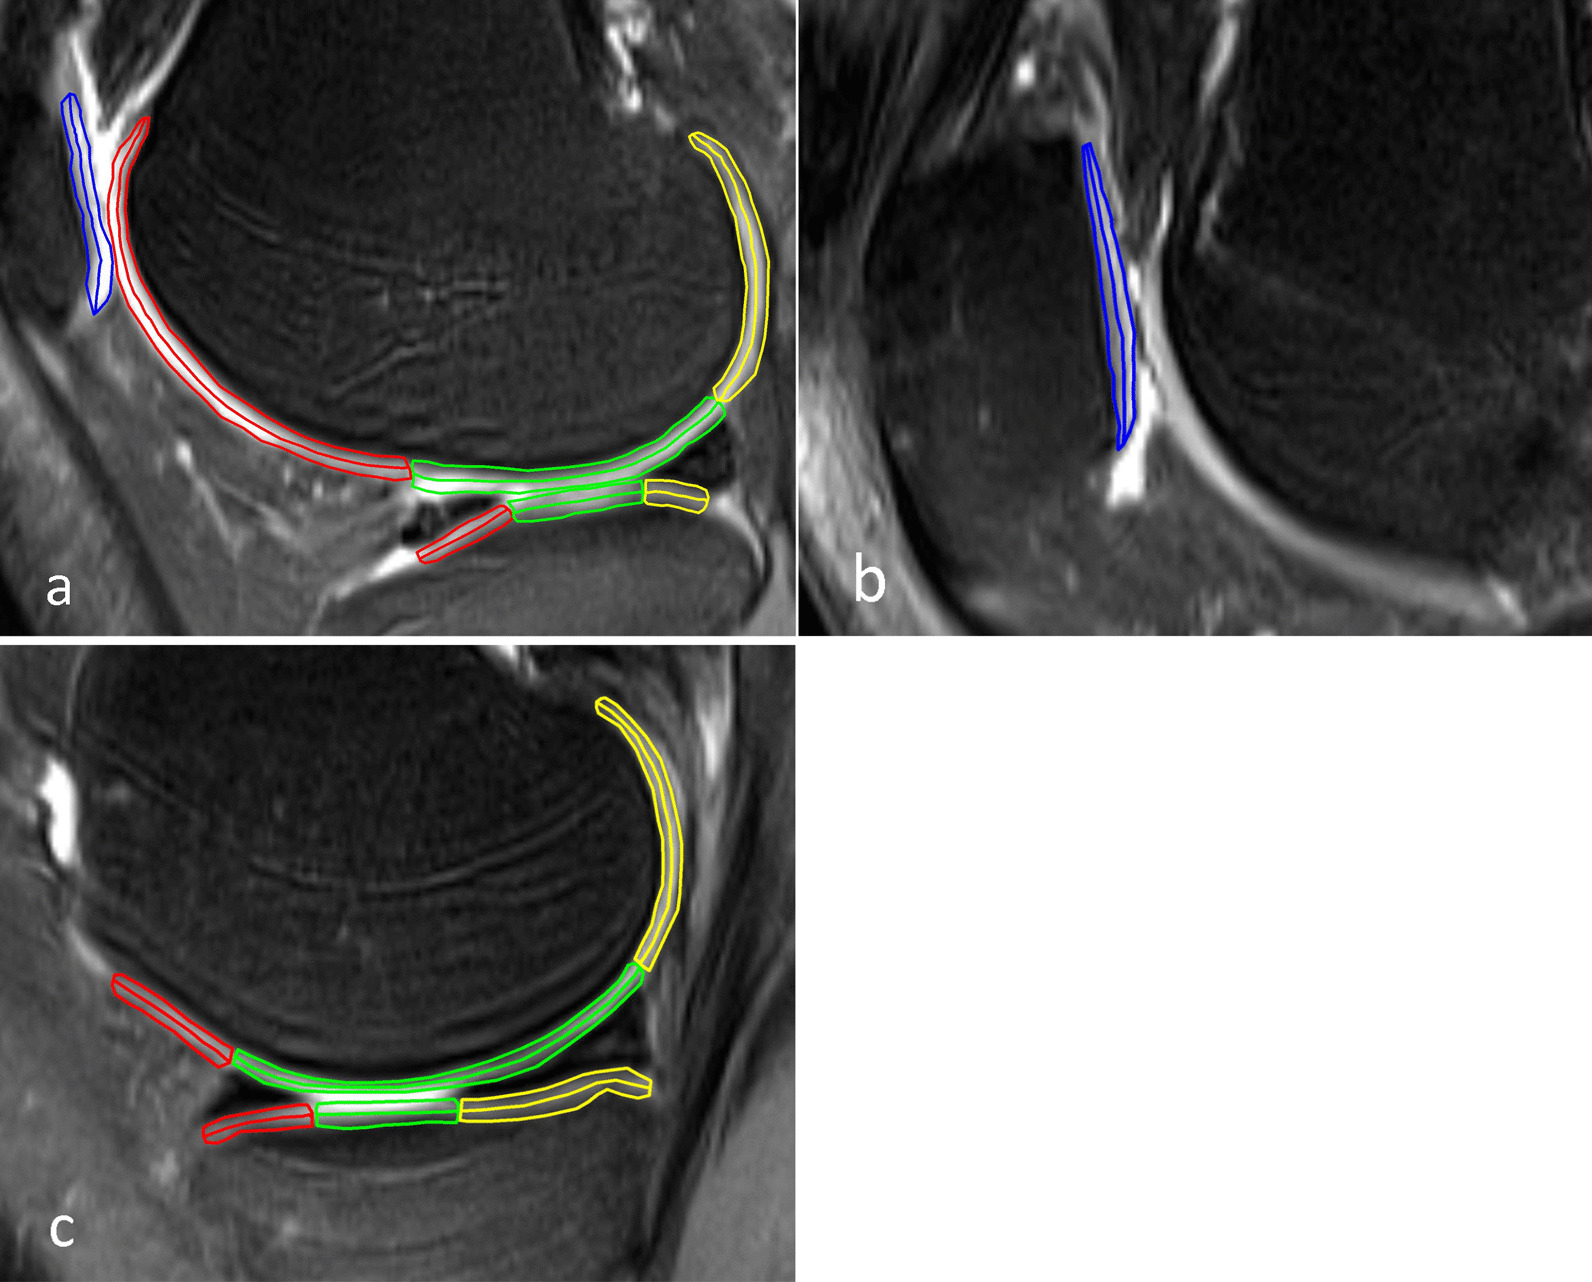

All the images were processed using the Syngo workstation (Siemens Medical Systems). Images from the control group were assessed by a senior radiologist to ensure absence of abnormal signals, motion artifacts or other unusual changes. Thereafter, two resident physicians dissected T2 maps of the articular cartilage into measurement regions of interest (ROI) according to Whole-Organ Magnetic Resonance Imaging Score [18]. Images of two groups were stored in the same workstation in the order of examination time, so two physicians blinded to whether the images came from the case or control group. Figure 1 was the regional subdivision of articular cartilage. The patella (P) was divided into medial (M) with the ridge and lateral (L) regions. The ridge of the patella is the cartilage contact point location which occurred along the centerline. The femur (F) and tibia (T) were divided into medial (M) with the trochlear groove and lateral (L) regions. Both the femur and tibia were further divided into anterior (a), central (c) and posterior (p) regions. The central femur referred to the region extending from the anterior edge of the anterior horn to the posterior edge of the posterior horn of the meniscus. The medial tibia encompassed the region that was not covered by the anterior and posterior corners of the meniscus while the lateral tibia included the region that was covered by the body of the meniscus. To make the data more profound, each region was equally divided into superficial (s) and deep (d) layers according to the thickness of cartilage. The superficial area is from the articular surface to the middle of the cartilage and the deep area is from the middle of the cartilage to the bone-cartilage interface [5]. Together, the cartilage of the knee joint was divided into twenty-eight subregions (Fig. 2 and Table 2). Each ROI was measured two times to obtain average T2 values. The selected layer had clear cartilage boundary with each subregion displayed to the greatest extent. Similarly, the T2 maps of the case group were measured using the same protocol. However, the images or the outcome of the conventional sequences were not evaluated before measuring the ROI of T2 maps.

Fig. 1.

Regional subdivision of articular cartilage

Fig. 2.

Sagittal fat-suppressed proton density weighted turbo spin-echo sequence images from the right knee cartilage of a 26-year-old male patient. Each region is equally divided into superficial and deep layer. Blue areas show lateral (a) and medial (b) patella cartilage. a and c illustrate lateral and medial cartilage of the tibiofemoral joint, respectively. Red, green and yellow areas represent the anterior, central and posterior cartilage, respectively. The ROIs size of this subject are 92, 105, 88, 102, 109, 102, 154, 148, 165, 168, 178, 183, 148, 133, 138, 130, 78, 83, 96, 98, 105, 94, 76, 77, 95, 97, 86, and 91 pixels (order according to Table 2)